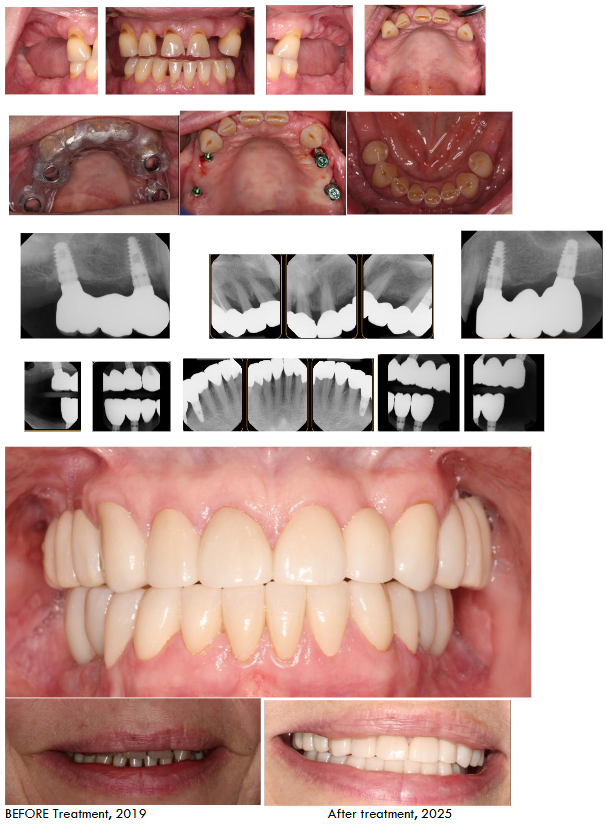

Four months later, after adequate healing and bone consolidation, 3D imaging taken by CareStream 9300 and surgical stent made by 3D Diagnostix Inc) used for strategically placing implant to support a fixed prosthesis (Implant Direct Legacy 2). Critically, in the mandible, the anterior teeth, while exhibiting some bone loss, demonstrated sufficient structural integrity and clinical attachment after thorough periodontal treatment. Therefore, a decision was made to retain these teeth, deviating from the “All-on-4” concept. This conservative approach aimed to preserve natural tooth structure, proprioception, and potentially improve the long-term stability of her teeth. The treatment sequence also considered the patient’s osteopenia and arthritis, favoring a less invasive approach where clinically justified.

Following implant osseointegration in the maxilla, final impressions were taken (Paradigm VPS Impression Materials from Darby Dental), for fabrication of implant-supported fixed prostheses. For conventional crown and bridges followed the zirconia guidelines and provisional prepared by lab. Prep done using course tapered diamond bur at high speed. Cemented crown and bridges using permanent cement (RMGI Nexus Cement).

Post-Treatment Follow-up and Outcome

The patient has been followed up for five years post-treatment. She has expressed high satisfaction with the functional and esthetic outcomes. She reports significant improvement in chewing ability, enhanced self-confidence, and a renewed ability to smile comfortably. Importantly, she has successfully discontinued vaping, demonstrating a commitment to improving her overall health. Her arthritis and osteopenia are being actively managed by her physician. The retained teeth have remained stable with regular periodontal maintenance, showing no signs of progressive bone loss or attachment loss. No biological or technical complications related to the implants or prostheses have been observed except for lower terminal implants in the third-year post treatment. The periimplantitis is treated like natural treat by flap elevation and debridement including regenerative periodontal therapy. The key to her successful is her commitment to three month recalls.